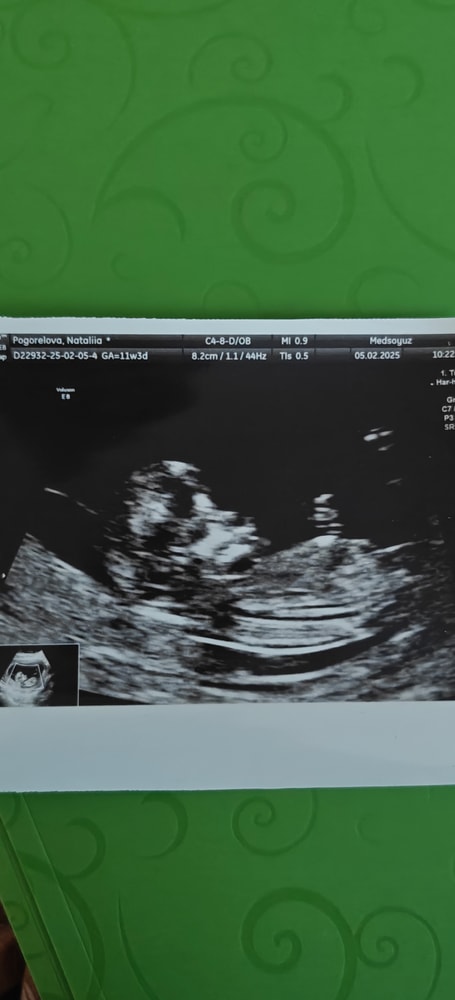

Алина

Мне кажется девочка. У мальчика как бы шарик на кончике, а у девочки вилочка, или бугорок вообще сужается к кончику. Вот это мальчик 11.1 срок.

Кажется у нас похожие ракурсы узи на этом сроке, прикладываю свой для сравнения посмотреть, на втором скрининге узнали, что у нас мальчишка! Хотя тут были все комментарии, что 100 % девочка. Так что ждите гарантированный второй скрининг 😁